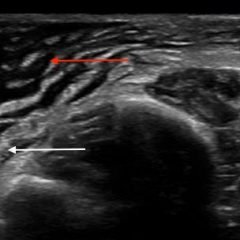

Physical exam was significant for an erythematous maculopapular rash in the right ophthalmic nerve (V1) region, a crusted vesicle at the right upper eyelid, and surrounding eyelid edema. Visual acuity remained at baseline and intraocular pressure was within normal limits. External slit lamp exam with fluorescein staining was remarkable for pseudodendrites in the inferior-temporal cornea approximately 1.5 mm from the limbus. Ophthalmology was consulted and completed an in-depth evaluation of the corneal lesions. They found no evidence of anterior chamber reaction and performed a complete dilated fundus examination which demonstrated no retinal involvement. The patient was then discharged on acyclovir and erythromycin ointment with close follow-up.